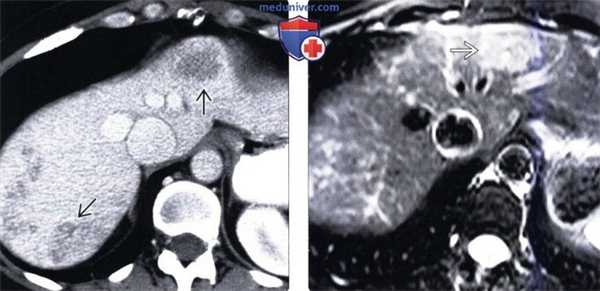

(Слева) На рисунке показаны расширенные печеночные вены и артерии, сообщающиеся друг с другом посредством извитых интрапаренхиматозных сосудистых каналов.

(Справа) На аксиальной КТ с контрастным усилением определяется раннее заполнение контрастом расширенных печеночных вен; видны также множественные мелкие телеангиэктазии («клубки» сосудов) — изменения, типичные для врожденной геморрагической телеангиэктазии. (Слева) На КТ срезе у этого же пациента визуализируется расширенная печеночная артерия, видны также многочисленные сплетения сосудов и более крупные сосудистые образования (лакуны). Эти изменения являются диагностическими для синдрома Рандю-Ослера-Вебера.

(Справа) На сонограмме (цветовая допплерография) визуализируются сосудистые «клубки», состоящие из расширенных и «переплетенных» друг с другом артерий и вен, а также шунты, по которым происходит «сбрасывание» крови в обход синусоидов.